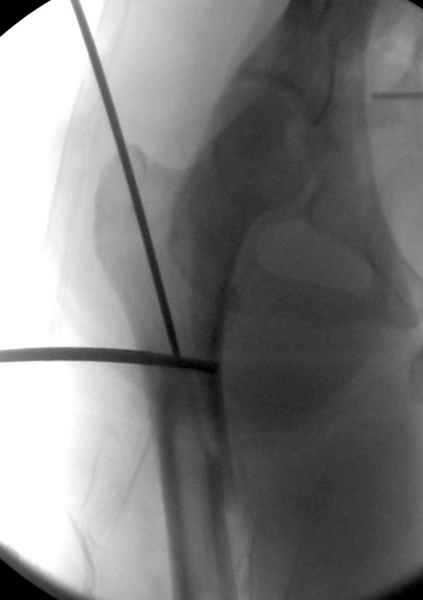

Как раз недавно у меня был примерный случай: больному 36 лет, поступил ночью, травма в результате мотоциклетной аварии, кроме чрезвертельного и спирального перелома левого бедра имеется переломы костей предплечья с этой же стороны. Скелетное вытяжение, а на следующий день больной про оперирован на ортопедическом столе с дистракцией. Чтобы не расколоть чрезвертельный перелом провели временную спицу ближе к переднему кортексу, из малого разреза костодержатель для репозиции, а фиксацию провели антиградным штифтом. Этапы операции на снимках.